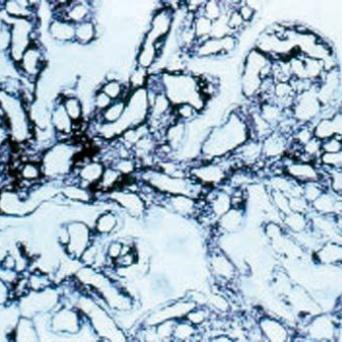

La stéatopathie métabolique est devenue la première cause de maladie chronique du foie. Le risque principal est la fibrose, qui, lorsqu’elle est sévère, peut évoluer vers une cirrhose et un carcinome hépatocellulaire. Qui faut-il dépister en soins primaires et comment interpréter les résultats ? Quelles options thérapeutiques ont fait leurs preuves ? Que peut-on attendre des nouvelles molécules ? Le point avec le Pr Stanislas Pol, hépatologue, hôpital Cochin, Paris.